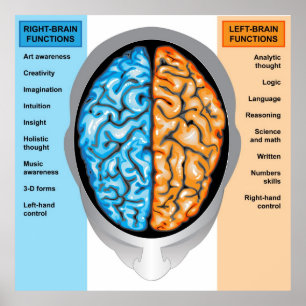

Poster Imagem Conceitual Do Cérebro Humano Em Diferentes

Preço27,75 €

Produto oficialmente licenciado